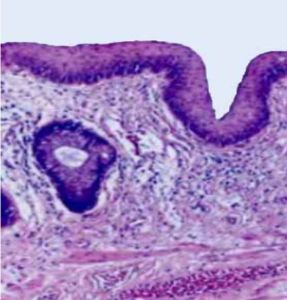

Perianal Area

Avoid TCA/Jessner’sThe perianal area is typically considered a dry area, as it has a low concentration of sebaceous (oil-producing) glands

However, it can become moist due to sweat, mucus, or hygiene-related factors

The skin in this area can be sensitive, so it's important to maintain proper hygiene without causing irritation

The perianal area is typically considered a dry area, as it has a low concentration of sebaceous (oil-producing) glands